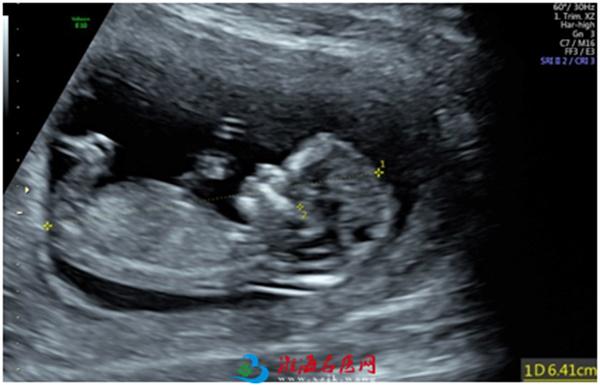

2. 胎儿颈部透明层(NT)

胎儿颈部透明层(NT)是早孕期超声筛查胎儿染色体异常的主要指标。也就是胎儿颈后皮下组织厚度。

NT增厚与唐氏综合征、先天性心脏病的危险性增高有关。

NT增厚,胎儿染色体异常的风险即增大,据有关文献记载,

*NT>0.35cm,胎儿染色体异常风险甚高

*NT=0.4cm,20%胎儿可能存在染色体异常

*NT=0.5cm,33%胎儿可能存在染色体异常

*NT=0.6cm,50%胎儿可能存在染色体异常

*NT≥0.65cm,65%胎儿可能存在染色体异常